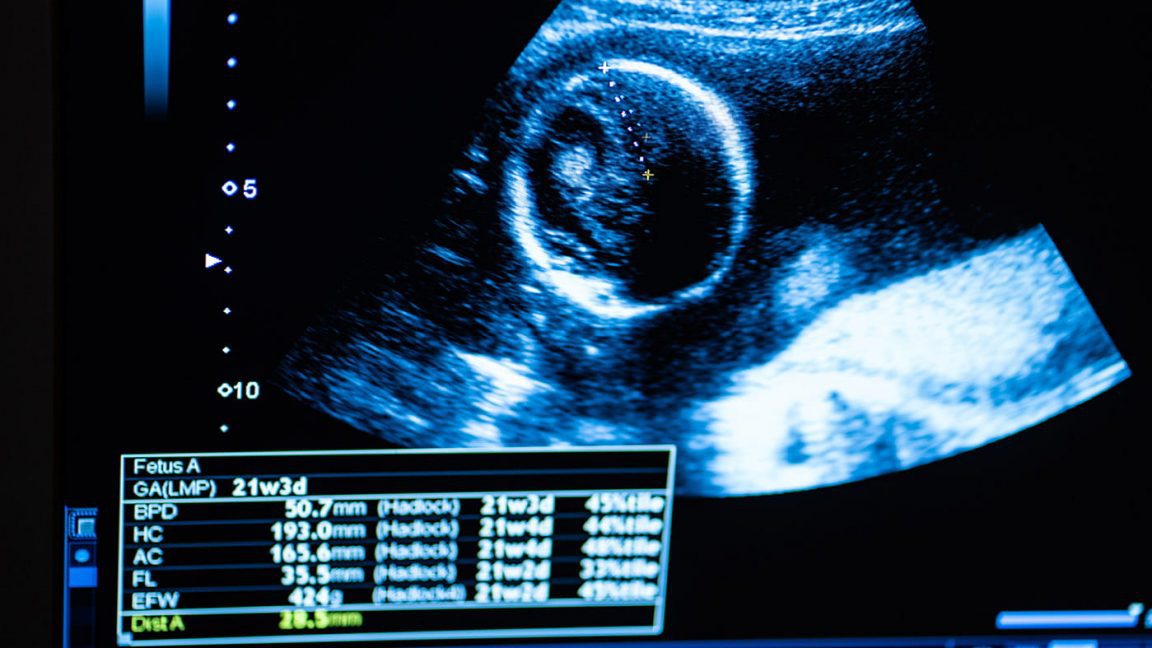

Врачи Восточно-Казахстанского специализированного медцентра успешно провели операцию женщине с редкой формой беременности – в шеечном пространстве, сохранив детородную функцию.

«Шеечная беременность – встречается редко и является опасным осложнением. Раньше единственным способом лечения было удаление матки. Сейчас мы выполняем высокотехнологичную медпомощь и спасаем детородный орган женщины. Здоровью пациентки ничего не угрожает, а в будущем она сможет родить здорового ребёнка», — подчеркнула заведующая отделением гинекологии ВК ОСМЦ Алия Кадырбаева.